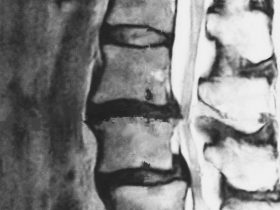

腰椎すべり症を伴う脊柱管狭窄症の原因と症状及び治療方法

「腰椎すべり症を伴う脊柱管狭窄症の原因と症状及び治療方法」 私たちの体は、年をとるにつれ、時間とともに変性することがあります。 その中の一部では、遺伝的要素のために特定の変性状態になることもあります。 …